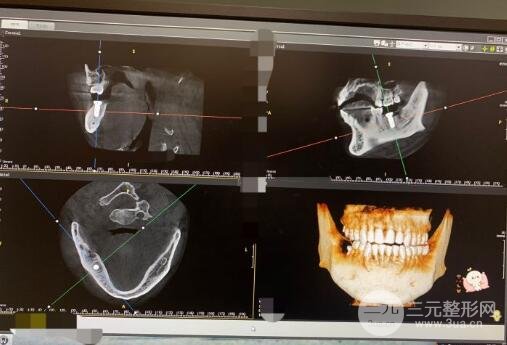

廣東省五官院整形成立于20世紀(jì)60年代。是廣東省口腔醫(yī)院的院長。它建立了一個種植中心,每年接待1萬名美容者。這在全國范圍內(nèi)是一個相對較大的數(shù)字。牙周病科也獲得了全國第二名。此外,它在預(yù)防齲齒和牙周病方面做出了突出的貢獻(xiàn),受到了美容人士的廣泛贊譽(yù)。